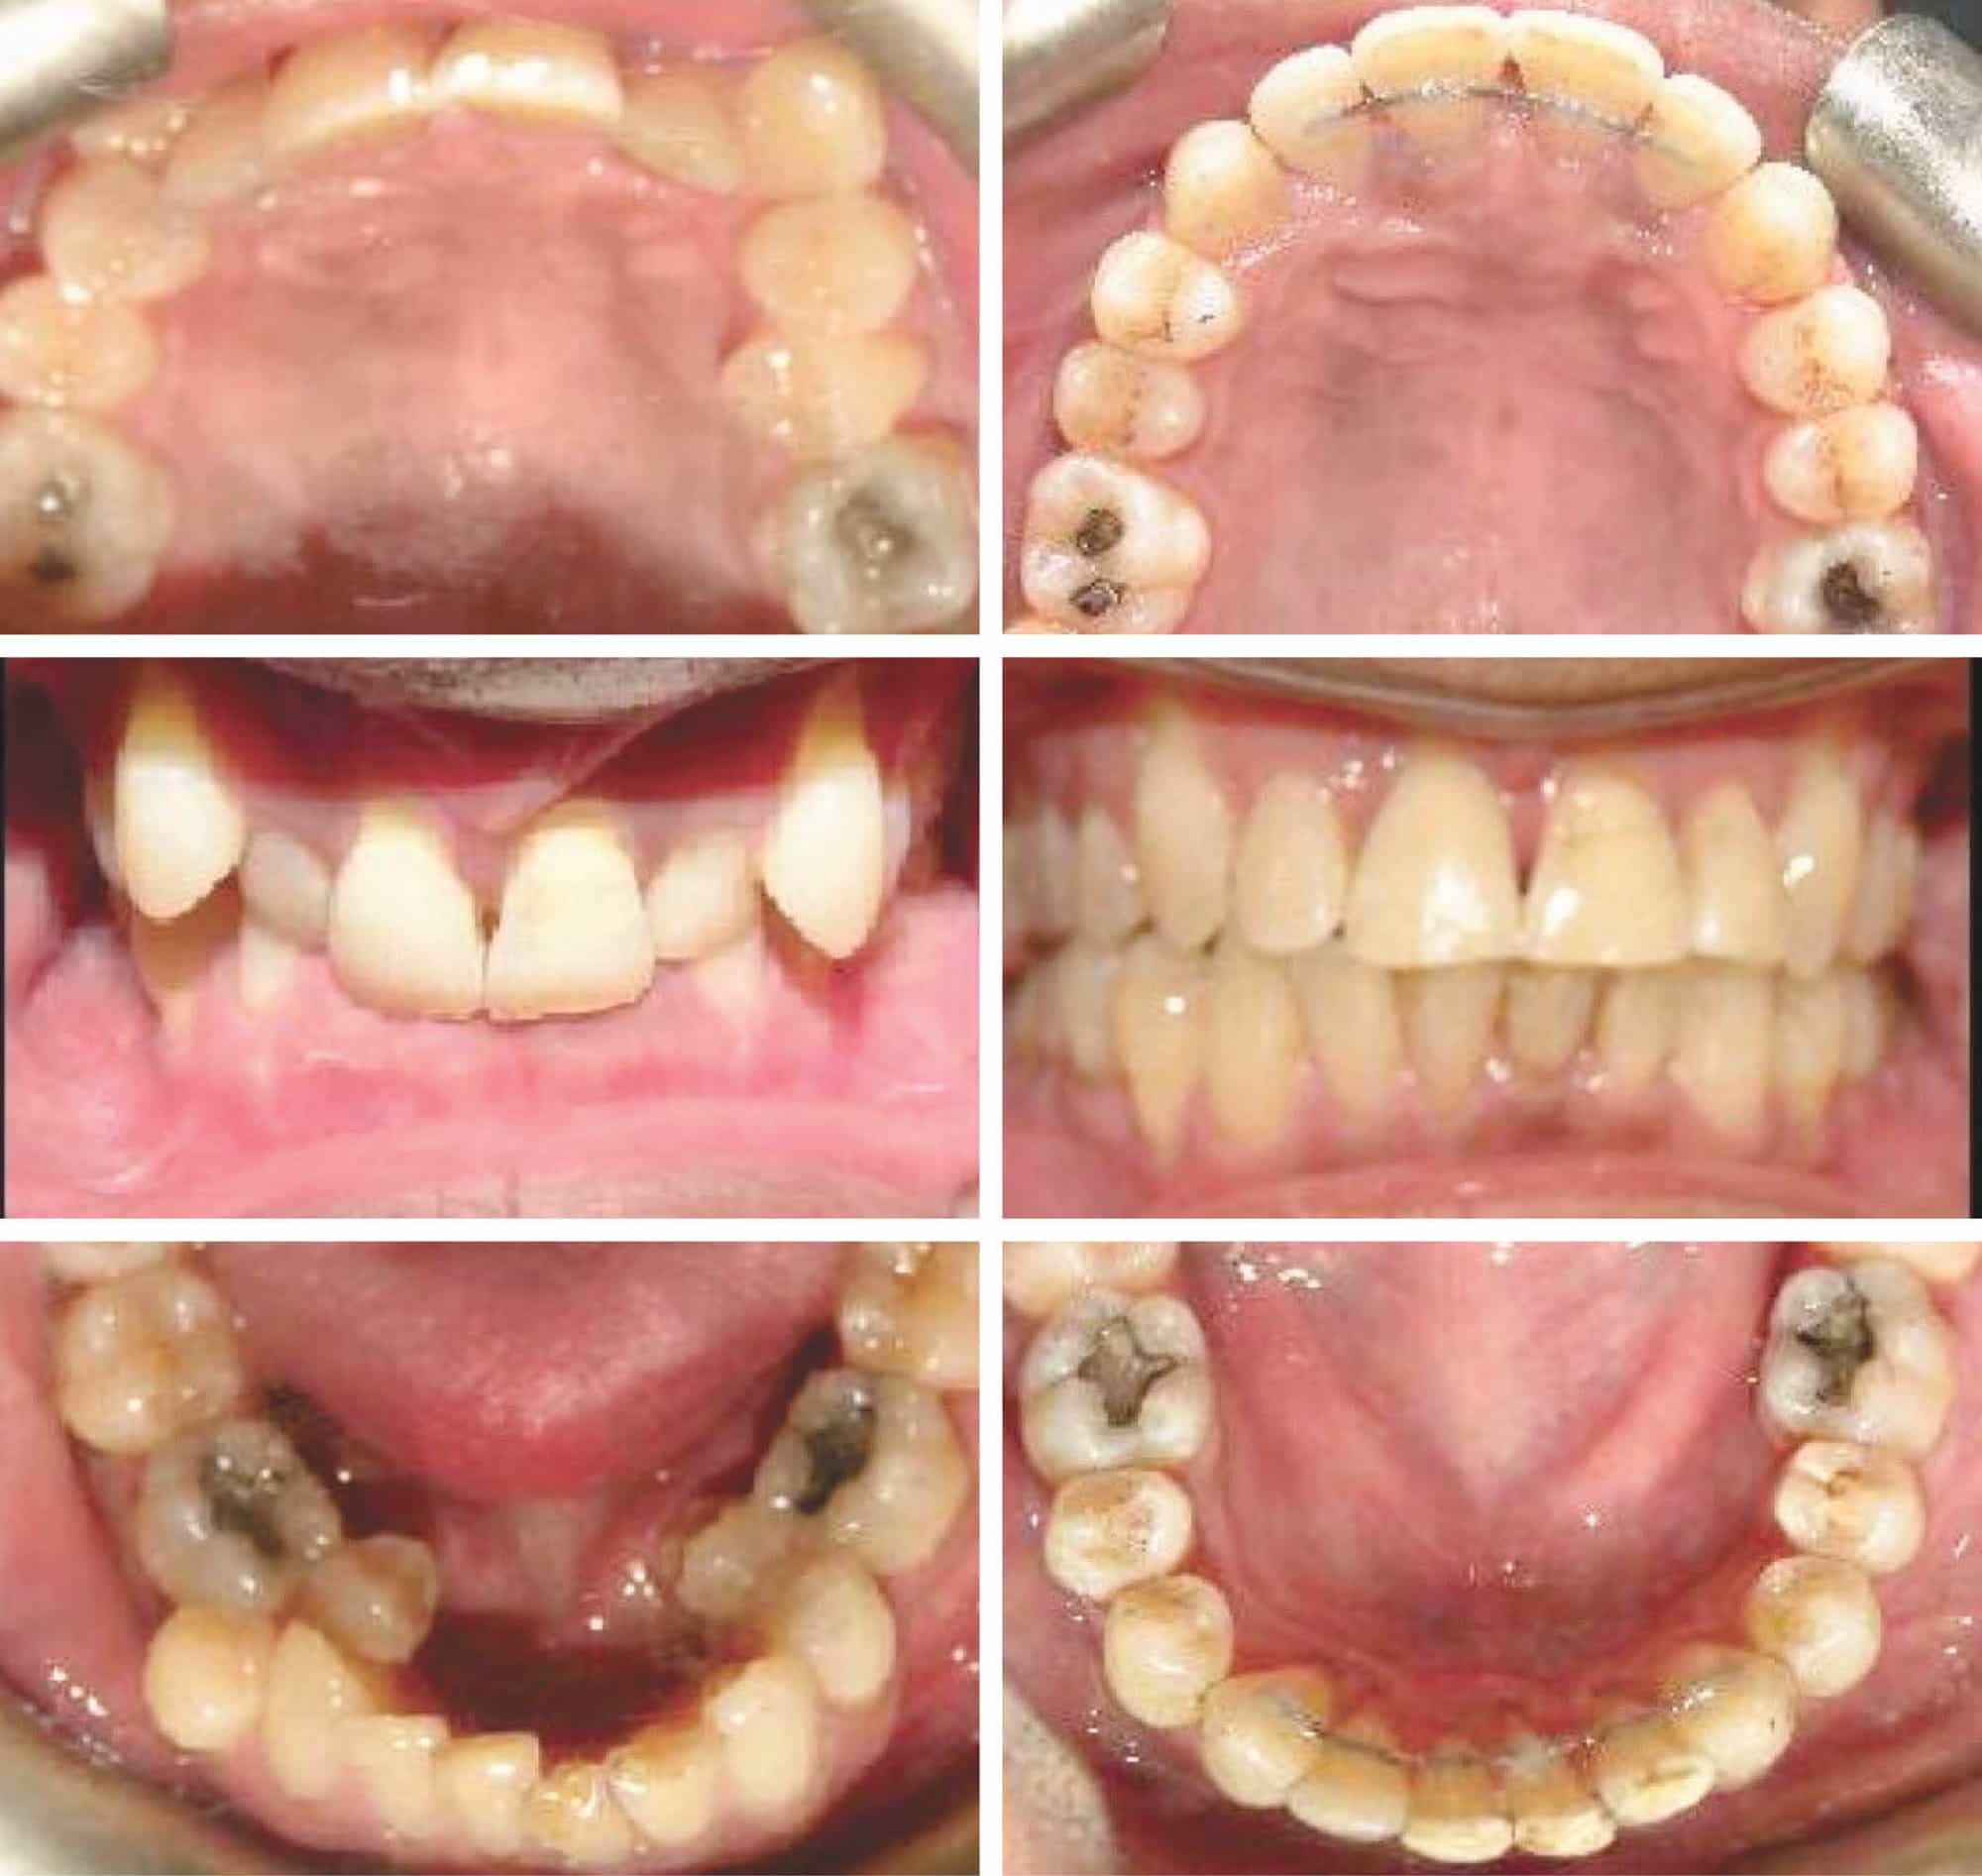

From aligndentistry.com.au

Upper and lower crowding of teeth with large overbite and Narrow arches , Align Dentistry Crowded Teeth And Overbite Make keeping teeth clean more of a challenge, increasing the. A deep bite, also known as an excessive overbite, is a type of malocclusion where the upper front teeth significantly cover the lower front teeth from top to bottom when the molars are. Dental crowding means your teeth don’t have enough room to grow in. Crooked teeth and misaligned bites. Crowded Teeth And Overbite.

Upper and lower crowding of teeth with large overbite and Narrow arches , Align Dentistry Crowded Teeth And Overbite Crowded teeth, a common orthodontic issue, occur when there is insufficient space within the dental arch to accommodate all the teeth. What is dental crowding (crowded teeth)? Malocclusion of the teeth is when. This condition often manifests as. Dental crowding means your teeth don’t have enough room to grow in. A deep bite, also known as an excessive overbite, is. Crowded Teeth And Overbite.